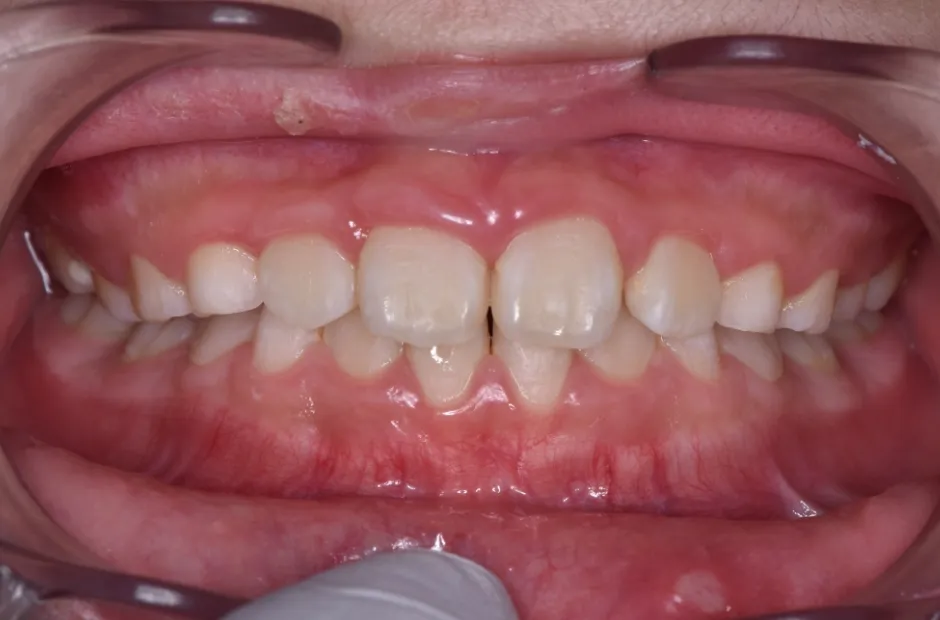

治療症例

ブラケット矯正

前歯部反対咬合

| 診断名・主訴 | 前歯部反対咬合 |

|---|---|

| 年齢・性別 | 14歳・男性 |

| 治療期間・回数 | 1年2か月 |

| 治療に用いた主な装置 | ブラケット矯正 |

| 抜歯部位 | なし |

| 治療費 | 60万円(税抜) |

| リスク・副作用 | 装置による違和感・疼痛・歯肉退縮・歯根吸収・虫歯のリスクなど |

治療前